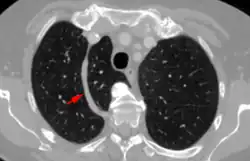

Während normalerweise die Vena azygos unmittelbar am Mediastinum von hinten nach vorne zur Vena cava superior zieht, verläuft sie bei dieser Variante durch den zusätzlichen Lappenspalt bzw. am Boden desselben. Wegen des Verlaufs dieses Azygosseptums von hinten nach vorne ist ein Lobus venae azygos im normalen Röntgenbild des Thorax in der Regel tropfenförmig gut erkennbar, wobei der Bauch des Tropfens der axial getroffenen Vena azygos entspricht.